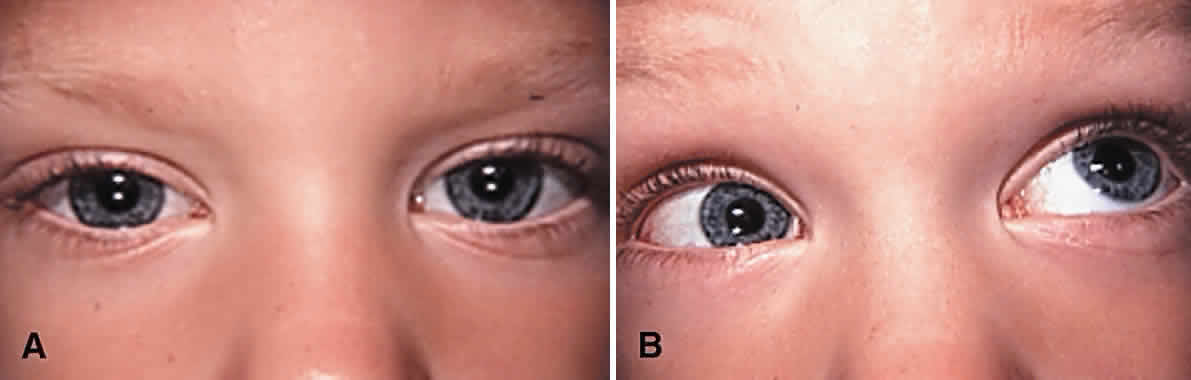

Surgery to correct unilateral, congenital superior oblique muscle palsy is the single most common indication for superior oblique muscle strengthening. It has traditionally been thought to be caused by dysfunction of the fourth (trochlear) cranial nerve. Patients typically present with an incomitant hypertropia characterized by elevation of the affected eye in adduction and overaction of the ipsilateral inferior oblique muscle. Diagnosis is normally supported (but not “diagnosed”) using Parks' three-step test.13 Compensatory torticollis is present in approximately 75% of cases, with the face turn or head tilt toward the opposite shoulder.14,15 This is often first noted when the child begins to walk. However, the presence of a vertical deviation in primary gaze position may be overlooked if the physician fails to evaluate ocular alignment with the child's head held erect. Chronic torticollis can result in asymmetric facial development and postural plagiocephaly (Fig. 1).16–18 Some authors believe that proper head positioning during sleep is more important than performing early surgery in preventing the facial asymmetry.19 It is not known whether early strabismus surgery can prevent or reverse this deformity.

|